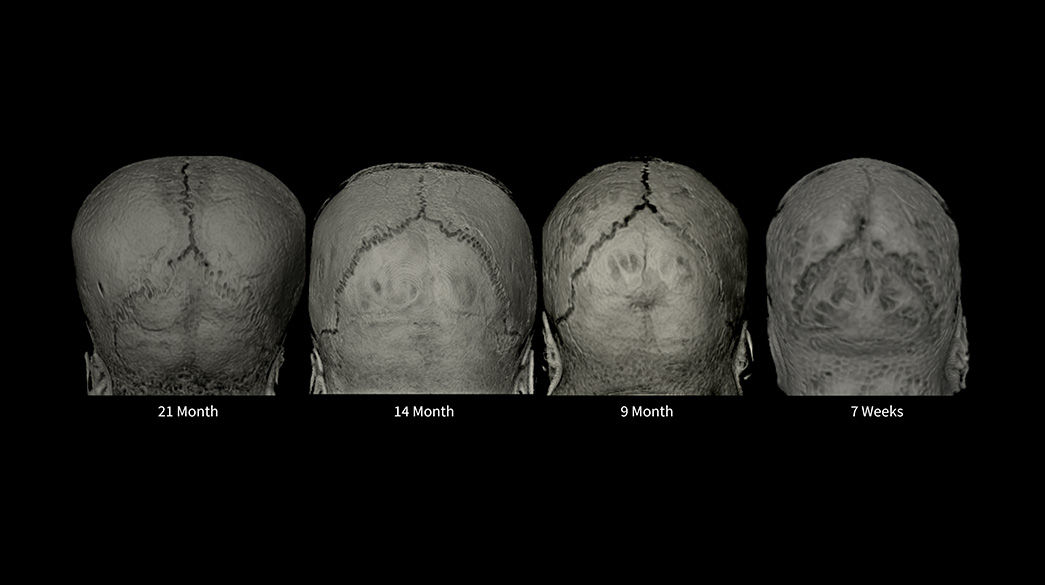

Consistent

Motion and distortion-reduced scans with high-resolution and contrast

Diagnostic confidence and consistency